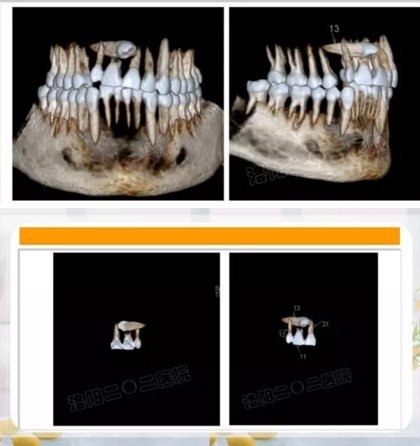

阻生齒外科聯(lián)合正畸治療

24.png

25.png

26.png

27.png

28.png